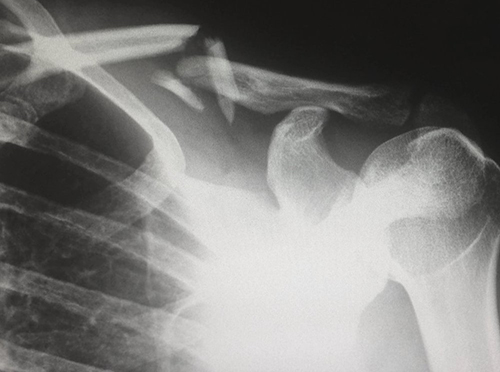

Институт медицинских исследований Гарвана обнаружил связь между когнитивным снижением и более быстрым темпом потери костной массы. Так когнитивное снижение в течение пяти лет увеличивает риск будущих переломов у женщин. Для мужчин данная связь слабее. Исследование людей в возрасте 65 лет и старше проводилось на протяжении 16 лет и выявило потенциально новый подход, помогающий определять людей, которые могут подвергаться риску перелома. Результаты были представлены в Journal of Bone and Mineral Research.

Ученые изучили когнитивные функций и здоровье костей у 1,7 тыс. женщин и 620 мужчин в возрасте 65 лет и старше, у которых не было симптомов снижения когнитивных функций в начале исследования.

Ученые обнаружили, что снижение когнитивных функций в течение первых пяти лет было связано с 1,7-кратным увеличением риска будущих переломов у женщин в последующие 10 лет.